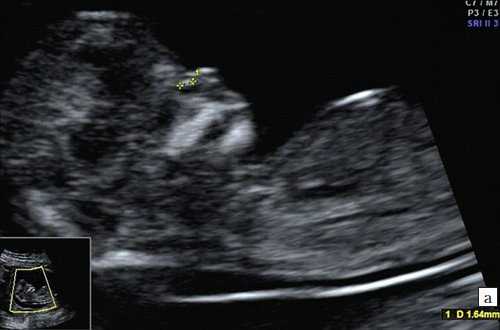

Копчико-теменной размер плода (КТР) для проведения скрининга I триместра должен быть в пределах 45-84 мм. Для оценки носовой кости в I триместре беременности необходимо соблюдать строгие условия. Это адекватное увеличение (на снимке должны быть только голова и верхняя часть грудной клетки), среднесагиттальный скан (должны быть визуализированы эхогенный кончик носа, небный отросток верхней челюсти, диэнцефалон), нос представлен тремя "К" (кончик носа, кожа, кость). Кожные покровы и кости носа визуализируются в виде знака "равенства", нос параллелен датчику.

Если все критерии соблюдены, то на уровне носа плода должны быть видны три четко различимые линии: верхняя линия представляет собой кожу, книзу от нее визуализируется более толстая и более эхогенная, чем кожа носовая кость. Третья линия, визуализируемая кпереди от носовой кости и на более высоком уровне, чем кожа - это кончик носа (рис. 1).

Рис. 1. Нормальная носовая кость.